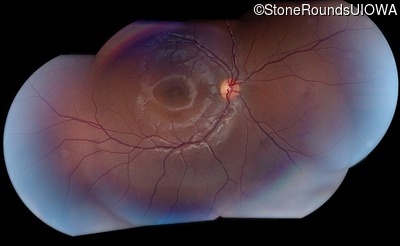

AR Stargardt Disease (IIA)

AR Stargardt Disease (IIA)

This 11 year old female first had difficulty seeing the blackboard at age 8. Later, she developed some photophobia.

Diagnosis & molecular findings

| Disease | Gene | Allele 1 variant(s) | Allele 2 variant(s) | Inheritance mode |

|---|---|---|---|---|

| AR Stargardt Disease | ABCA4 | Gly1961Glu GGA>GAA, Arg212Cys CGC>TGC | Gly1961Glu GGA>GAA, Arg212Cys CGC>TGC | AR |